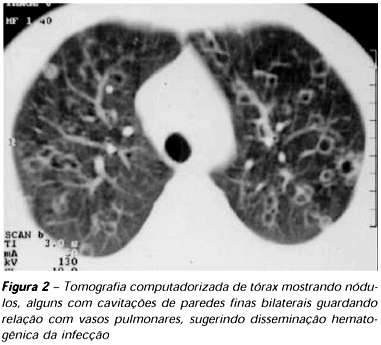

1. Esses casos muitas vezes são diagnosticados após a retirada cirúrgica por suspeita de carcinoma pulmonar. Outros 5% desses pacientes evoluem com formação de cavidades de paredes finas, solitárias e justapleurais, podendo regredir espontaneamente em cerca de 2 anos. Em alguns casos, principalmente em pacientes diabéticos ou imunocomprometidos, a forma pulmonar aguda não regride, evolui para uma pneumonia crônica e caracteriza-se pela formação de cavidades pulmonares.

1. Os pulmões também podem ser acometidos difusamente, como resultado da inalação de uma grande quantidade de artroconídios infectantes ou como apresentação tardia e secundária resultante de disseminação hematogênica. Essas formas apresentam-se com múltiplos infiltrados difusos, os maiores podendo apresentar cavidades que cursam com manifestações respiratórias graves, que podem levar a insuficiência respiratória, e são mais comumente observados em pacientes imunocomprometidos. A evolução pode ser fulminante, mimetizando choque séptico, ao lado da síndrome da angústia respiratória aguda, com elevada letalidade.